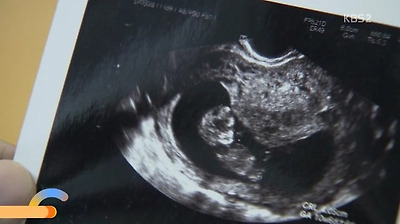

임신성 빈혈은

초기부터 조심하는게 좋아요

임신이요...?

제가 아이를 가졌다구요..?

네 그럼요

모르셨어요?

아이가 잘 자라고 있네요

임신 3개월이라며

의사쌤은 아이의 심장소리를

자신과 도윤의 아이에게

세연이는 도윤이에게 초음파 사진을 건네줌

하진이하고..내 아기네...

사진 속 아이를 만지며

넘나 기뻐하는 도윤이ㅠㅠㅠ